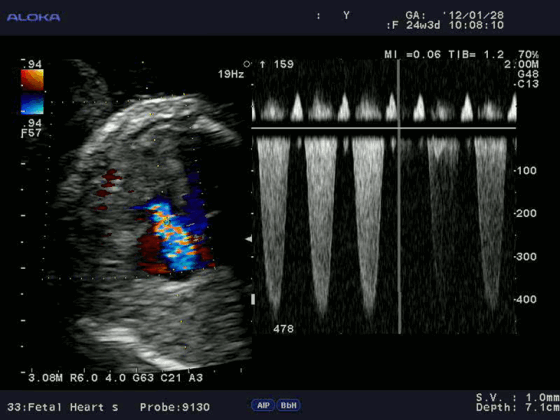

Допплерэхокардиография позволяет измерить все вышеперечисленные параметры, которые очень важны при оценке детской сердечной патологии (врожденные пороки) без использования инвазивной процедуры — катетеризации сердца. Помимо этого, назначение эхокардиографии с допплеровским анализом ребенку не несет никакой угрозы по сравнению с компьютерной томографией, где используется рентгеновское излучение.